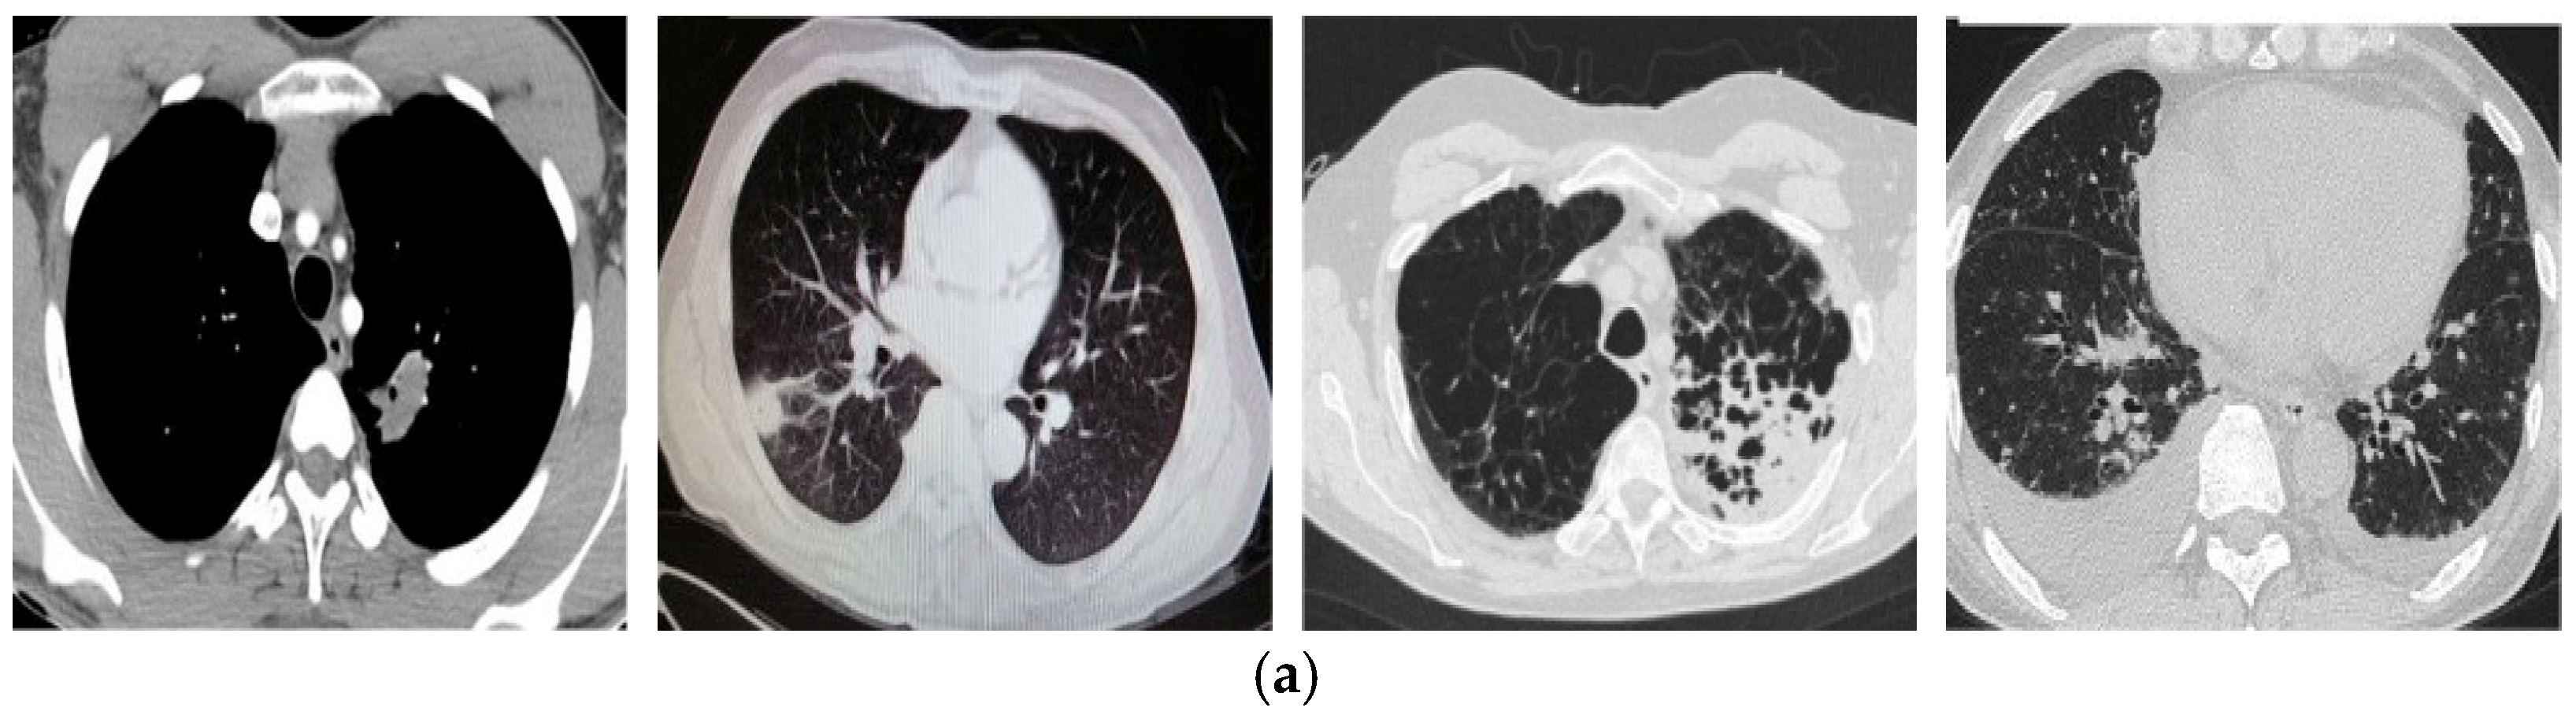

4.1. Datasets

- Zhao, J.; Zhang, Y.; He, X.; Xie, P. Covid-ct-dataset: A ct scan dataset about COVID-19. arXiv 2020, arXiv:2003.13865. [Google Scholar]

- Song, Y.; Zheng, S.; Li, L.; Zhang, X.; Zhang, X.; Huang, Z.; Chen, J.; Zhao, H.; Jie, Y.; Wang, R. Deep learning enables accurate diagnosis of novel coronavirus (COVID-19) with CT images. IEEE/ACM Trans. Comput. Biol. Bioinform. 2021, 18, 2775–2780. [Google Scholar] [CrossRef]

- COVID-19 CT Segmentation Dataset. Available online: http://medicalsegmentation.com/covid19/ (accessed on 10 October 2023).